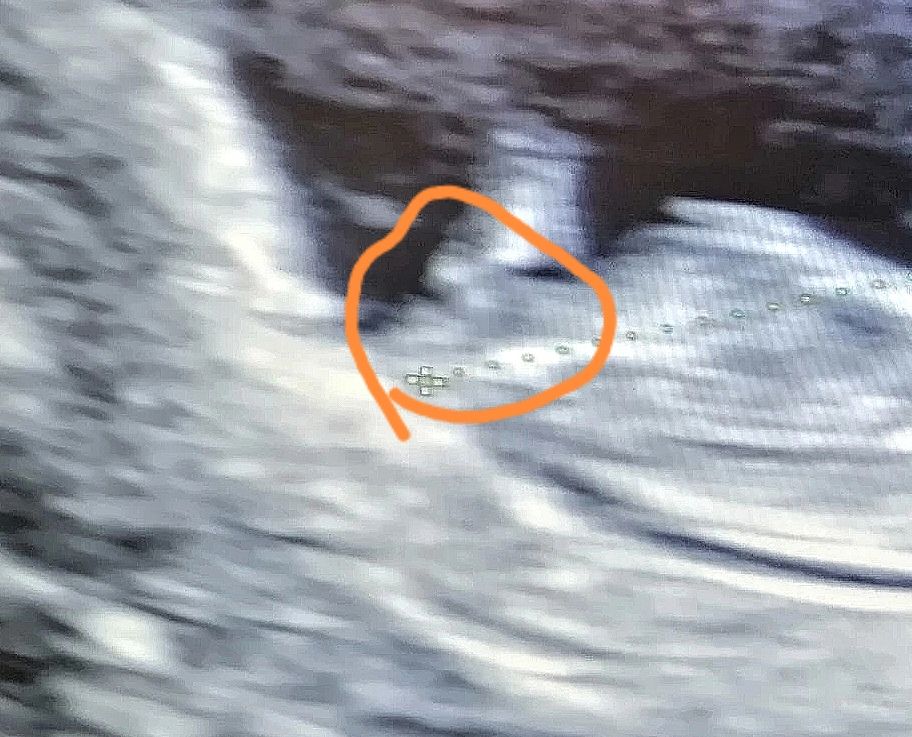

Изображение Девочка) У меня у парня прям наверх смотрел) А у вас вперёд будто) Через месяц сообщите😂 Но, прям 90% девочка

Анастасия, спасибо большое за ответ, могу попросить вас на моем фото так же вот в кружок обвести бугорок этот?) а то я не знаю туда смотрю или нет)

19.05.2023

Изображение Алиса,

Половой бугорок я вроде вижу, если это он. Но пол предположить не решусь, т.к. наклон хоть и небольшой, но есть, а это и мальчик может быть, и девочка 🤷